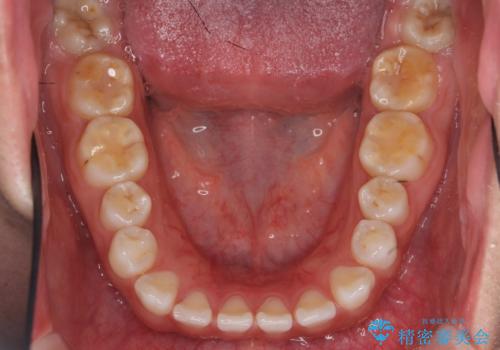

インビザライン 気になるすきっ歯の改善

- 上下顎前歯部の空隙が気になるので治したいと当院にいらっしゃった方の症例です。

非抜歯、インビザラインによる矯正治療により歯と歯の隙間および前歯の上下の隙間を閉じ切りました。